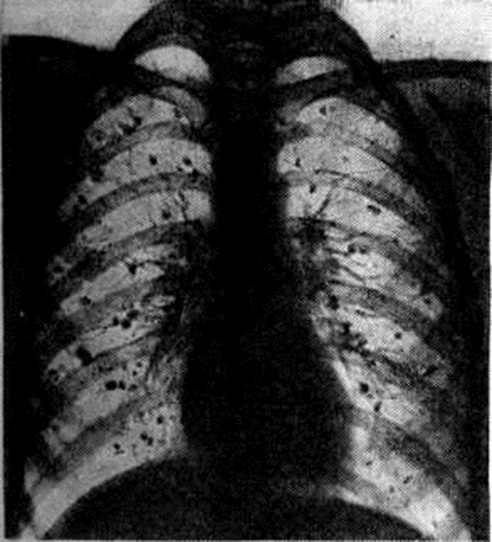

ИммунитетГистоплазмоз характеризуется развитием в инфицированном организме высокой специфической иммунологический резистентности, что обусловливает у подавляющего большинства заболевших бессимптомное или субклиническое течение инфекции, низкий уровень смертности. Гистоплазма обладает сенсибилизирующими свойствами, внутрикожная аллергическая проба с гистоплазмином (смотри полный свод знаний Кожные пробы) становится положительной через 2—3 недель после заражения и продолжает оставаться положительной на протяжении многих лет. В крови больных образуются комплементсвязывающие антитела, преципитины, агглютинины. Серологические реакции с гистоплазмином используют для определения иммунологический состояния больного. Так, положительная РСК (смотри полный свод знаний Реакция связывания комплемента) в высоких, возрастающих титрах указывает на диссеминированный Гистоплазмоз и имеет прогностическое значение. У лиц, перенёсших Гистоплазмоз, развивается обычно длительный иммунитет. Клиническая картинаИнкубационный период длится 1—2 недель, иногда больше. В связи с ингаляционным путём инфицирования наиболее часто поражаются лёгкие. Первичный внелёгочный Гистоплазмоз наблюдается очень редко, поражения кожи, слизистых оболочек, кишечника представляют обычно проявления диссеминированного Гистоплазмоз Различают два основных типа: первичный Гистоплазмоз лёгких — часто встречающийся, доброкачественный, и вторичный диссеминированный прогрессирующий Гистоплазмоз — редкий, тяжёлый, часто смертельный тип болезни. Первичный Гистоплазмоз лёгких у 80% инфицированных протекает бессимптомно. Первичный лёгочный комплекс по величине и форме очень похож на первичный туберкулёзный комплекс, выявляется в виде небольшого ограниченного субплеврального очага чаще всего в нижней и средней долях лёгких. Первичный Гистоплазмоз лёгких распознается обычно лишь методом внутрикожной пробы с гистоплазмином; но, несмотря на бессимптомное течение, у многих больных через 3—5 лет в лёгких (рисунок 4) развиваются множественные мелкие кальцинаты (обызвествление бугорков), иногда обнаруживаемые в печени и селезёнке. У 20% инфицированных первичный Гистоплазмоз лёгких сопровождается общими симптомами различной тяжести.

В легко протекающих случаях клинической, картина проявляется катаром верхних дыхательных путей с небольшим повышением температуры тела, кашлем, головной болью в течение недели. В более тяжёлых случаях — лихорадка ремиттирующего типа, озноб, пот, кашель с гнойной мокротой, иногда с кровью, головная боль, слабость, анорексия. В лёгких — инфильтраты одиночные и множественные по типу бронхопневмонии, лобулярной, лобарной пневмонии с регионарной лимфаденопатией. Физикальные данные минимальны; клинической, и рентгенологическое картина сходны с атипической пневмонией (смотри полный свод знаний), туберкулёзом лёгких (смотри полный свод знаний Туберкулёз органов дыхания); инфильтрат при Гистоплазмоз локализуется в нижних и средней долях лёгких, позднее инфильтрат рассасывается или обызвествляется. Течение болезни — несколько недель, месяцев. Тяжёлые случаи острого первичного двустороннего Гистоплазмоз лёгких наблюдались во время вспышек инфекции в эндемических очагах. Хронический форма первичного Гистоплазмоз лёгких характеризуется длительным лечением (1—2 года и более) с периодами обострений и ремиссий. В лёгких образуются инфильтраты, тонкостенные кистообразные полости, наряду с этим в лёгких и прикорневых узлах развиваются фиброз, кальцинаты (смотри полный свод знаний Пневмосклероз). Больные испытывают резкую слабость, падает вес тела, развивается анемия, лейкопения. Эта форма в 0,1—0,2% случаев переходит в диссеминированный, системный Гистоплазмоз Клинической, картина острой стадии диссеминированного Гистоплазмоз характеризуется высокой лихорадкой с изнурительным потом, адинамией, анемией, истощением, увеличением печени, селезёнки (смотри полный свод знаний Гепато-лиенальный синдром), генерализованной лимфаденопатией. Рентгенологическое картина сходна с фиброзно-кавернозным туберкулёзом лёгких. У 20% больных диссеминированной формой Гистоплазмоз обнаруживаются язвенное поражение слизистых оболочек рта и глотки, гортани, тонкого кишечника, абсцедирующие инфильтраты в подкожной клетчатке, язвенно-вегетирующие поражения кожи лица, носа, наружных половых органов, трещины ануса. Нередко поражаются кости (в виде кистообразных полостей), суставы, часто — костный мозг, надпочечники. К тяжёлым осложнениям относится поражение центральная нервная система (менингит, энцефалит), сердца (приобретённые пороки сердца, эндокардит), глаз (ретинит, хориоидит). У детей Гистоплазмоз протекает тяжелее, с наклонностью к генерализации, чаще и резче выражены гепато-лиенальный синдром, генерализованная 1 лимфаденопатия, поражение кишечника, кожи. Диагноз и дифференциальный диагноз основывают на обнаружении в мокроте внутриклеточно расположенных дрожжевидных клеток Histoplasma capsulatum при окраске по Гимзе (смотри полный свод знаний Романовского — Гимзы метод), промывных водах бронхов, желудка, мазках гноя; при хронический диссеминированной форме — в стернальном пунктате, мазках крови (лейкоконцентрате), моче, кале, цереброспинальной жидкости. При распространённых поражениях органов возбудитель обнаруживается в крови больных, причём внутрикожная реакция с гистоплазмином отрицательна. Подтверждает диагноз получение культуры возбудителя при посеве тех же материалов на среду Сабуро, кровяной агар и другие. Очень важны внутрикожные пробы и серологические исследование, особенно РСК с гистоплазмином, биопсия (из слизистой оболочки бронха, краёв язв, лимф, узлов и другие). Тканевую форму гистоплазмы нужно дифференцировать с лейшманией (смотри полный свод знаний Лейшманиозы), криптококками (смотри полный свод знаний Криптококкоз), при этом наиболее достоверные результаты даёт окраска по методу Гомори — Грокотту. Важны результаты прививки костного мозга и других биопсированных тканей мышам, а также географический и профессиональный анамнез. Первичный лёгочный Гистоплазмоз дифференцируют с респираторной инфекцией (смотри полный свод знаний Респираторные вирусные болезни), бактериальной пневмонией. Хронический форму и диссеминированный Гистоплазмоз дифференцируют с другими системными микозами (смотри полный свод знаний), лимфогранулематозом (смотри полный свод знаний), другими болезнями ретикулоэндотелиальной системы, раком. Во всех случаях Гистоплазмоз дифференцируют с туберкулёзом лёгких. При этом учитывают характерные для Гистоплазмоз локализацию очагов в нижней, средней долях лёгких, тонкостенные полости (при отрицательной реакции Манту и отсутствии в мокроте микобактерий туберкулёза), множественные мелкие кальцинаты в лёгких, распространённую лимфаденопатию, гепатолиенальный синдром, язвенные поражения кожи, слизистой оболочки рта, глотки, кишечника, наружных половых органов; все эти симптомы развиваются на фоне лихорадки, анемии, лейкопении, кахексии, волнообразного течения процесса. ЛечениеПри первичном Гистоплазмоз больные подлежат госпитализации. Применяют сульфаниламидные препараты, особенно сульфазин, норсульфазол в суточной дозе 4—6 грамм, нистатин внутрь в виде суспензии (в воде) и в виде ингаляций или аэрозоля натриевой соли нистатина или леворина. При распространённой тяжёлой форме и диссеминированном Гистоплазмоз— повторные курсы амфотерицина В в виде внутривенных капельных вливаний (при плохой переносимости внутримышечных инъекций); применяют также переливание крови, эритроцитарной массы, инъекции гамма-глобулина, поливитаминотерапию, усиленное белковое питание. Антибиотики назначают только кратковременно для подавления вторичной бактериальной флоры, причём стрептомицин противопоказан. ПрогнозПервичный Гистоплазмоз лёгких протекает доброкачественно, в основном бессимптомно; при редко наблюдающемся тяжёлом течении прогноз также почти всегда благоприятный, особенно при своевременном распознавании. При диссеминированном Гистоплазмоз прогноз сомнительный или плохой, особенно у детей и пожилых людей, а также при поражениях центральная нервная система, надпочечников; при лечении повторными курсами амфотерицина В в ранней стадии диссеминации процесса прогноз лучше. ПрофилактикаОбеззараживание почвы во дворах городов, парках, лагерях и другие трёхкратной обработкой 3—5% раствором крезола, формальдегида (двухчасовая экспозиция); покрытие площадок асфальтом или насаждение травы, деревьев, других растений. При работе в эндемичном участке, в пещере, микологический лаборатории — пользование респираторами (смотри полный свод знаний), противогазами (смотри полный свод знаний). Из эндемичных районов не допускается вывоз почвы и удобрений. Проводятся исследования по применению живых вакцин для иммунизации населения угрожаемых районов.